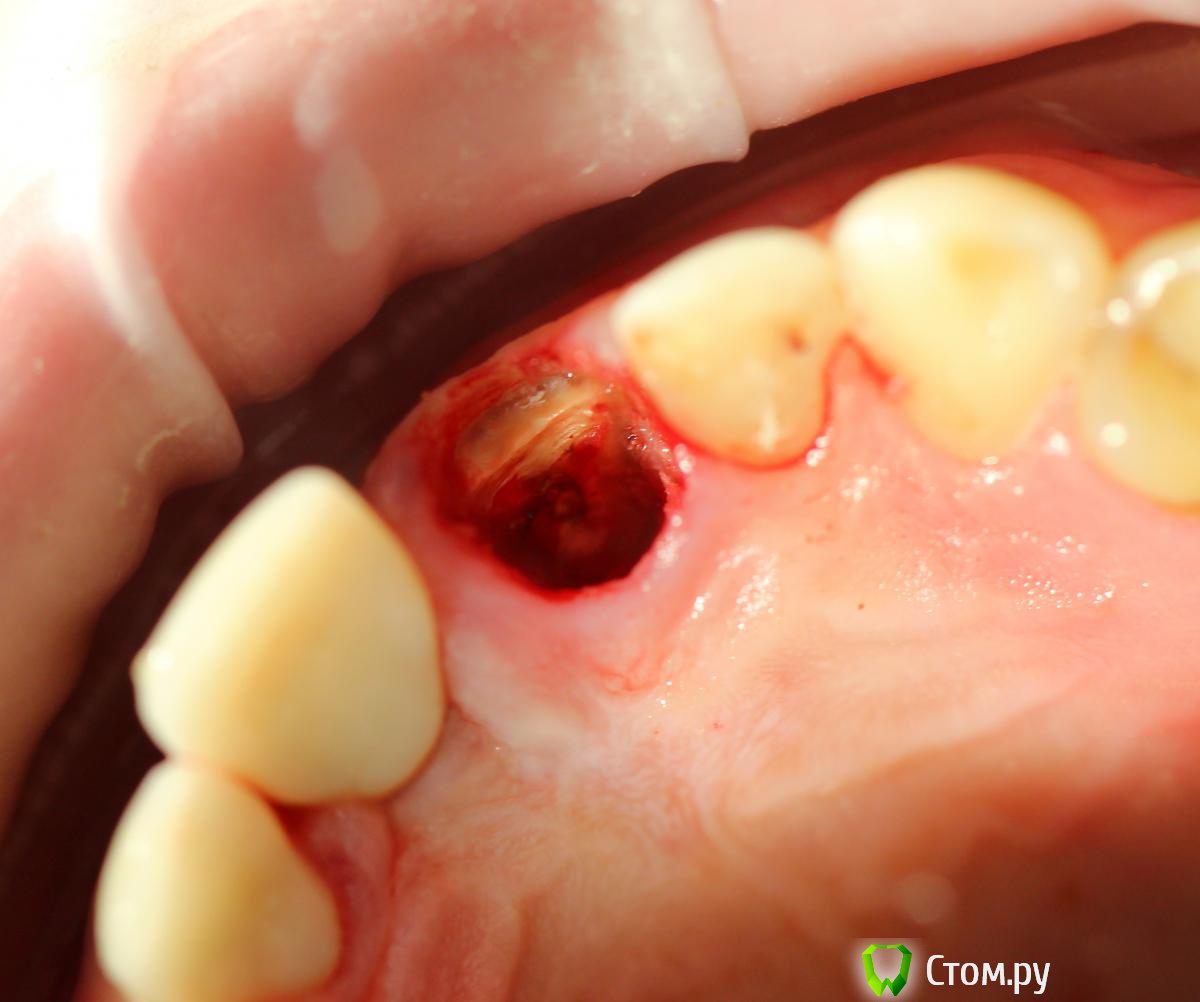

Andex Опубликовано 7 октября, 2014 Поделиться Опубликовано 7 октября, 2014 Внесу свой взгляд на тему. Мне интерестна методика - выкладываю свой кейс. Солидарен с Александром, если Вам интерестно - могу поделиться результатами и наблюдениями своих пациентов. На последнем фото - установил формирователь, тк через неделю после операции разошлись швы и сместился мною плохо мобилизованный ротированный(недостаточно) лоскут с неба - мои навыки еще далеки от идеала. Ссылка на комментарий

Дмитрий Никитюк Опубликовано 7 октября, 2014 Поделиться Опубликовано 7 октября, 2014 Внесу свой взгляд на тему. Мне интерестна методика - выкладываю свой кейс. Солидарен с Александром, если Вам интерестно - могу поделиться результатами и наблюдениями своих пациентов. На последнем фото - установил формирователь, тк через неделю после операции разошлись швы и сместился мною плохо мобилизованный ротированный(недостаточно) лоскут с неба - мои навыки еще далеки от идеала. А в чём, собственно, Ваш взгляд? Ссылка на комментарий

Andex Опубликовано 8 октября, 2014 Поделиться Опубликовано 8 октября, 2014 (изменено) а почему в этом случае отдали предпочтение щитку?Конфигурация гребня хорошая, рядом коронка на болте в хорошем состоянии, вкрутил бы болт немедленно + графт в щель + сст, + врем коронка. ИмХоМне понравилась теория данной методики- поэтому я пока отношусь к числу людей,кто верит в щит. Рядом винт - тоже моя работа, сделал специально 2 зуба рядом в одинаковых условиях(на одном пациенте), чтобы динамику в сравнении наглядно вести. Графт+сст+времянка - пока считаю свой уровень недостаточным для таких продвинутых методик, в основном из-за сст,тк не научился еще с ним работать как надо(( Изменено 8 октября, 2014 пользователем Andex 1 Ссылка на комментарий